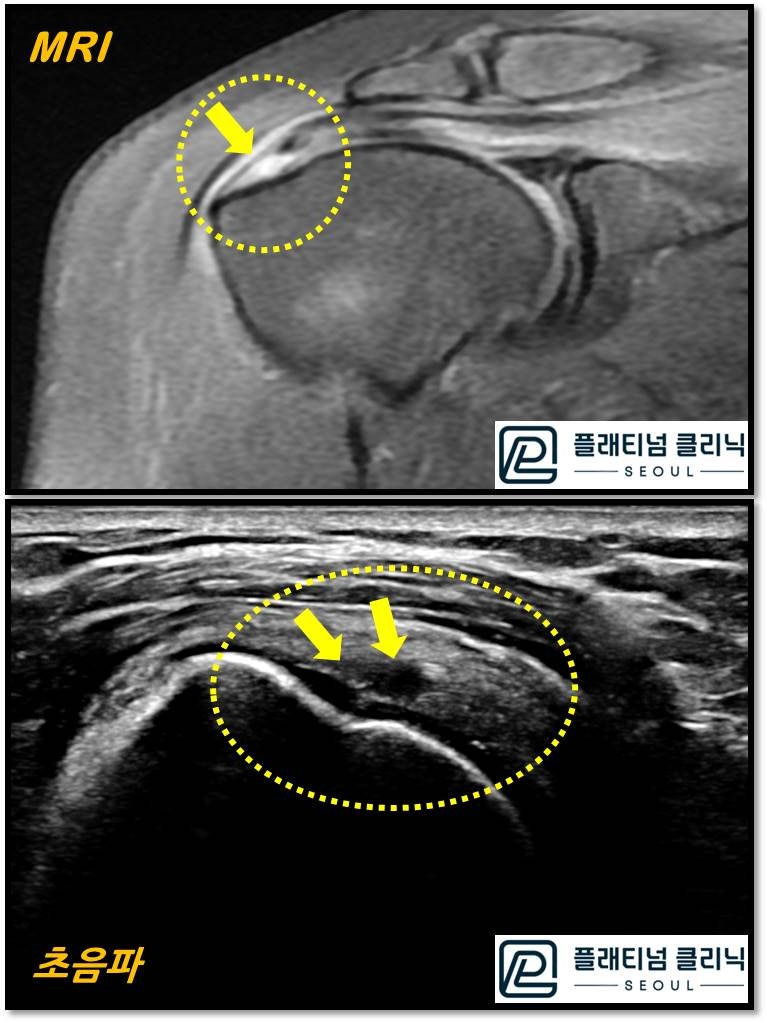

같은 환자 회전근개 파열에서 단면을 자른 영상을 비교한 것입니다. 한눈에 봐도 초음파가 더 크고 선명하게 보이지 않으신가요? 파열된 부위가 훨씬 선명하게 잘 보입니다. 이것 뿐 아니라 초음파는 연속적으로 검사를 하기 때문에 미세한 석회나 염증, 파열등을 MRI 보다 더 잘 진단할 수 있습니다. MRI 에서는 파열이 큰 경우나 석회가 큰경우(4mm 이상) 진단이 되나 그 이하에서는 진단이 어렵습니다. 물론 초음파를 보는 술자에 따라 차이는 있을 수 있습니다. 경험이 많은 정형외과 의사라면 충분히 MRI 없이 회전근개 질환의 진단을 초음파로 할 수 있습니다.